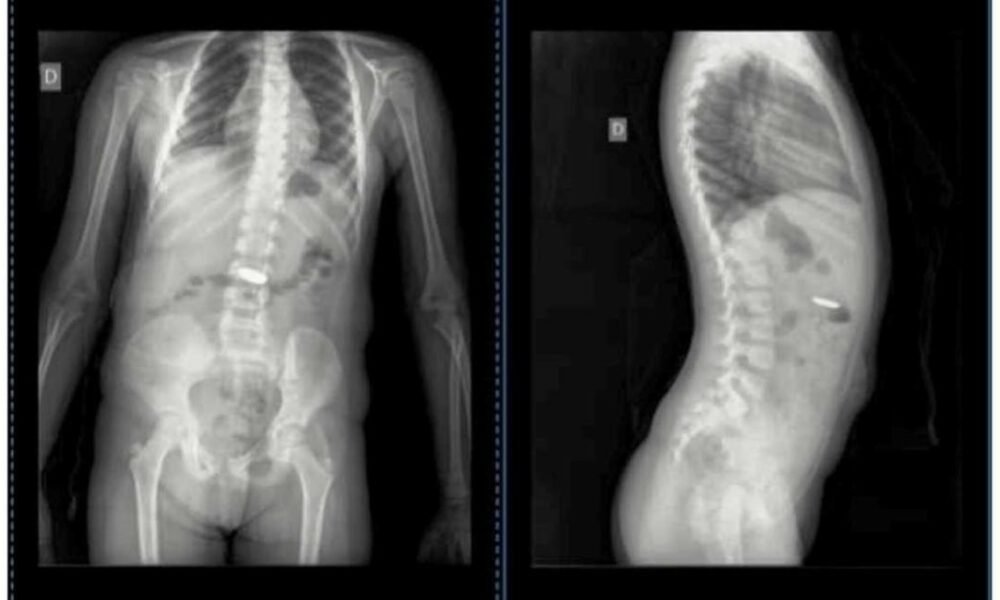

En un mensaje compartido en su cuenta de Facebook, Silvina expresó su frustración ante la incomprensible situación: “Siete médicos en Chascomús vieron las imágenes de las radiografías que le hicimos a Isabella por el tema de la pila ‘botón’ que se tragó. ¡Sí, siete! Cuatro en la Guardia y 3 por mensaje, solo uno, al que le pasé por mensaje ayer, supo ver lo que pasaba”.

Finalmente, Silvina decidió llevar a Isabella al Hospital de Niños de La Plata, donde el Dr. Jorge Ortale, reconocido profesional con una trayectoria de 54 años en el campo de la medicina, pudo detectar la presencia del objeto extraño en la radiografía de la niña. El traslado y la intervención en el Hospital de Niños de La Plata resultaron exitosos, permitiendo la extracción de la pila de manera segura. Silvina expresó su alivio y agradecimiento hacia el Dr. Ortale por su competencia y acertado diagnóstico.